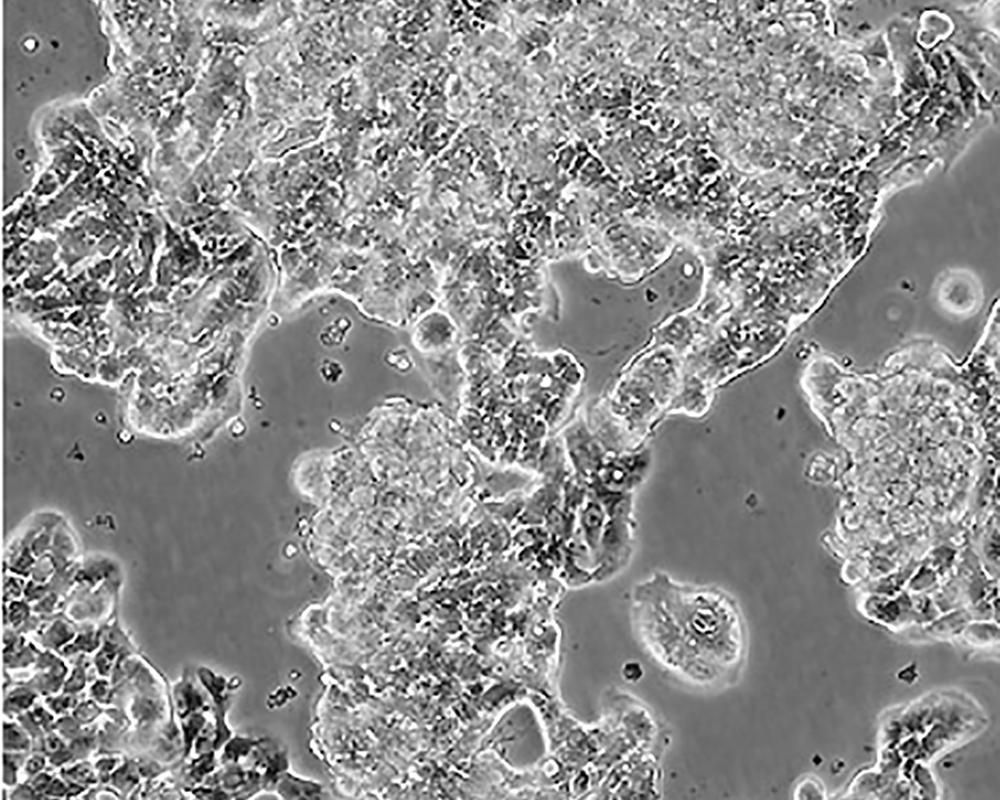

ZR-75-1 [ZR751]

中文名稱 人乳腺癌細(xì)胞

組織來源 浸潤性導(dǎo)管癌;腹水轉(zhuǎn)移;女性

生長特性 adherent

形態(tài)特征 epithelial

細(xì)胞描述 該細(xì)胞產(chǎn)生高水平的黏液素MUC-1 mRNA,低水平的MUC-2 mRNA,但不表達(dá)MUC-3基因;表達(dá)雌激素受體。